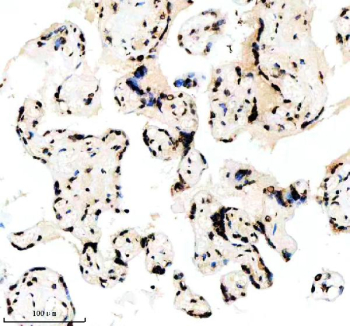

IHC analysis of Histone H3 (acetyl K14) using anti-Histone H3 (acetyl K14) antibody. Histone H3 (acetyl K14) was detected in a paraffin-embedded section of human placenta tissue. Heat mediated antigen retrieval was performed in EDTA buffer (pH 8.0, epitope retrieval solution). The tissue section was blocked with 10% goat serum. The tissue section was then incubated with a dilution of 1:50 rabbit anti-Histone H3 (acetyl K14) antibody overnight at 4oC. Peroxidase Conjugated Goat Anti-rabbit IgG was used as secondary antibody and incubated for 30 minutes at 37oC. The tissue section was developed using an HRP secondary and DAB substrate.